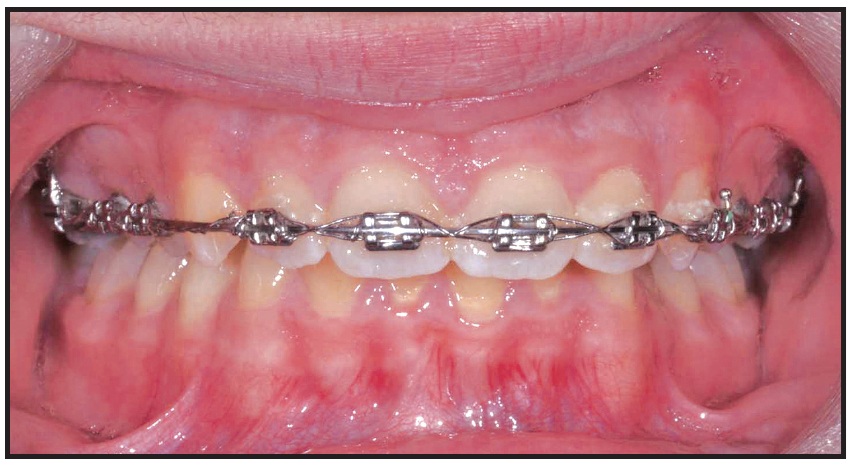

Preadjusted .022" × .028" brackets*** were placed in the upper arch, and an .014" nickel titanium archwire was used to correct the upper incisor inclination and the scissor bite (Fig. 2). After five months of treatment, a Herbst appliance with four 1.4mm × 6mm TADs† (H4T) was placed (Fig. 3). In the lower arch, one miniscrew was inserted between the right first permanent molar and second premolar and the other between the left first and second premolars. Auxiliary buttons were bonded to the buccal surfaces of the canines, and elastic chains were attached to the miniscrews to retrocline the lower incisors and promote mandibular protraction. In the upper arch, a miniscrew was inserted between the first and second premolars on each side, and elastic chains were attached between the miniscrews and an .018" × .022" stainless steel archwire for vertical control.

Fig. 2 .022" × .028" brackets*** placed in upper arch.

Fig. 4 Failed upper left TAD replaced after 11 days with TAD between canine and first premolar.

Fig. 5 Herbst appliance removed after 10 months of treatment.